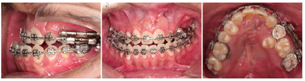

1.转诊行牙周洁治;颌面外科拔除12及18、28、38、48;采用标准直丝弓矫治技术,上下牙列粘托槽及磨牙带环,逐步更换弓丝,排齐整平上下牙弓;

2.外科辅助放置牙支持式牵张器(图5):上颌弓丝换至0.019*0.025"SS",外科于左侧24、26根尖下0.5mm处做梯形切口,行骨皮质切开术,粘接牙支持式骨牵张器;牵张器由螺旋扩弓器(杭州新亚,0.4 mm螺距)制成,打磨抛光多余金属部件,焊接于24、26带环;术后7 d开始加力,每日1次,每次旋转1/2圈,2周复诊1次。

3.开辟足够间隙,稳定后开始唇向牵引25(图6)。

4.术前调整(图7):25纳入牙弓,去除牵张器,继续排齐整平牙列,匹配牙弓,去除咬合干扰;患者口腔卫生差,给予牙周洁治,加强口腔宣教。